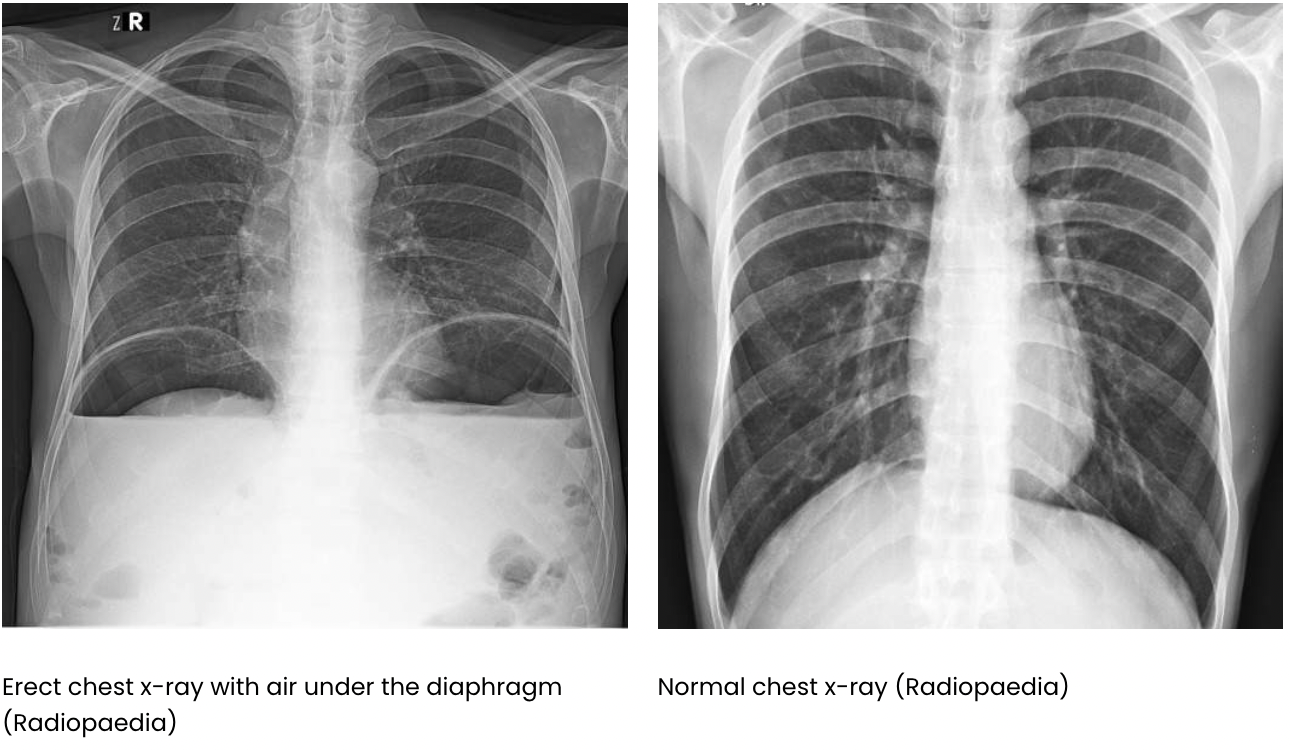

What do you think that free air under the diaphragm might indicate?

Free air under the diaphragm may suggest a possible perforation of the bowel (either stomach or gut as they hold air in these spaces) and this can lead to air leaking out and building up under the diaphragm.

There is also possible duodenal ulcers or peptic-duodenal ulcers which may also possibly be the cause of this.

Free air is example of pneuomoperitoneum.

The diagram of the X-ray shows how air build up under the diaphragm causes air to push up against arched diaphragm and flattens the muscle.

Why do we do an erect chest x-rays in humans?

This allows air to rise to top of the abdomen and the air is seen delineating the diaphragm (i.e. you can see both sides of the diaphragm where usually only one would be visible.

If the individual is too unwell to stand for a chest x-ray, a lateral decubitus film will do the same as the lateral abdominal radiograph in dogs.